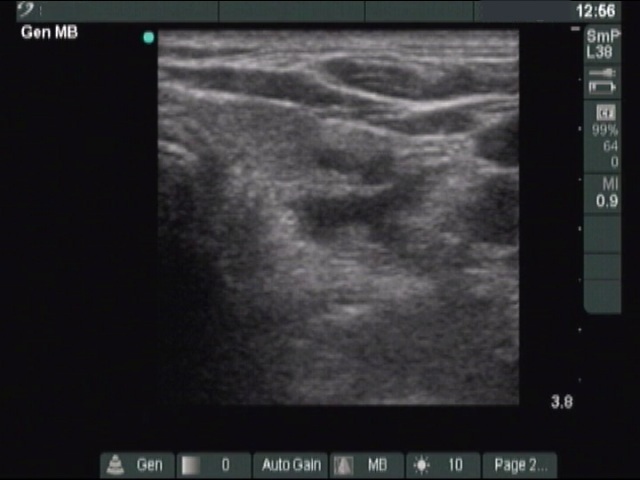

Right lobe, horizontal view

Lower pole of the right lobe, horizontal scan. The cystic lesion dorsal to the echonormal thyroid is the parathyroid cyst.